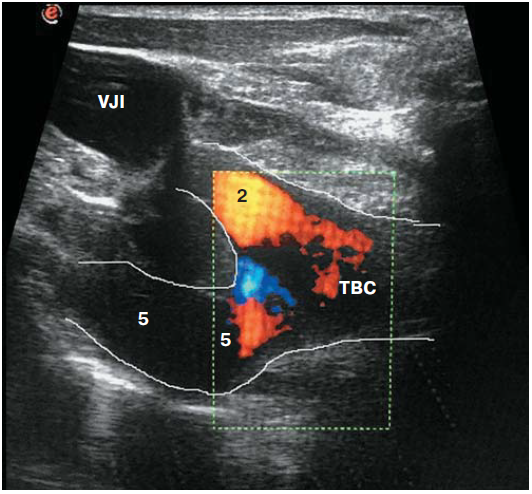

Больная Б., 36 лет, поступила 29.03.2017 для планового оперативного лечения с диагнозом: “Нетоксический многоузловой зоб 2-й степени (ВОЗ). Синдром механической компрессии органов шеи”. УЗИ: общий объем железы – 72 см3 (правая доля – 52 см3). Правая доля представлена крупным солидным образованием, обильно васкуляризированным, 52 × 46 × 42 мм, гипоэхогенной структуры (TIRADS 4b). В левой доле множество разноэхогенных узлов округлой формы до 15 мм в диаметре (TIRADS 2–3). Лимфоаденопатии не выявлено.ТАБ узлов правой и левой долей – коллоидный зоб (категория II, Bethesda Thyroid Classification). На дооперационном этапе выполнена КТ органов шеи и верхнего средостения без контрастирования. Отмечено смещение трахеи и сосудистого пучка шеи. Выполнена тиреоидэктомия. Операция начата с мобилизации верхнего полюса правой доли с селективной перевязкой сосудов. При мобилизации доли визуализирована структура толщиной до 2–3 мм и длиной до 10 см. Последняя начиналась выше перстнещитовидного соединения и имела вертикальное направление, интимно прилегала к капсуле железы. Эта структура была принята за НВГН (рис. 5а). При дополнительной мобилизации доли в области связки Бэрри выявлен типичный ВГН, который образовывал анастомоз с первично выявленной структурой (рис. 5). Ретроспективно пациентка обследована. При УЗИ выявлено устье брахиоцефалического ствола (Y-признак) (рис. 6). При непрямой ларингоскопии, УЗИ гортани – подвижность связочного аппарата сохранена. Клинических и лабораторных признаковгипокальциемии (общий кальций на 1-е сутки – 2,2 ммоль/л) не выявлено. Пациентка выписана на 3-и сутки после операции. При гистологическом исследовании в правой доле выявлена микро-нормофолликулярная аденома, в левой доле – ткань ЩЖ с морфологической картиной разнофолликулярного коллоидного зоба.

Рис. 6. УЗИ с цветным картированием. Выявлен Y-признак: 2 – правая общая сонная артерия, 5 – правая подключичная артерия, VJI – внутренняя яремная вена, TBC – брахиоцефалический ствол.